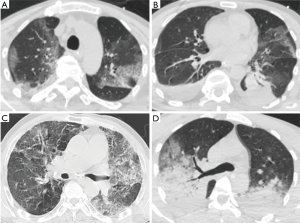

Imaging findings

No specific patterns of pulmonary infiltration were noted in cases with HRV-associated pneumonia. Both diffuse patchy infiltrations and lobar consolidations were observed in the chest computed tomography (CT) images, as revealed in Figure 3. Pleural effusion revealed in five cases. There were no statistical differences between the two groups, as detailed in Table 2.

In this series, respiratory failure was remarkably common and 12 cases (7 in the viral group and 5 in the viral-bacteria group, P=0.612) were classified into SCAP. No significant difference was observed in the prevalence of SCAP in the group with HRV-detection group and in the group without HRV-detection (Figure 2). The results indicated that HRV may have an essential role in the pathogenesis of SCAP, even in mono-infection. In addition, despite the viral group had higher clinical severity scores of pneumonias on admission, the viral-bacterial group turned out to have longer ICU LOS and hospital LOS, and worse clinical outcome. The result was consistent with former studies (1,32,34). Polymicrobial infections in CAP are generally considered to cause more severe inflammation and tissue damage than single microbial infections as observed in our study, patients in the viral-bacterial group had more elevated CK than in the viral group. But it is still an open question whether the clinical manifestations are related directly to viral pathogenicity, or the viral infection just predisposes the patient to bacterial pneumonia, as observed in influenza virus pneumonia (35). Further studies need to be done to illustrate the underlying pathogenesis. Lastly, no special laboratory workup or particular patterns of radiographic changes were observed in HRV-associated pneumonia. Leukocytosis and elevated PCT were common even in the viral group, and pulmonary consolidation appeared in CT images with or without bacterial co-infection.